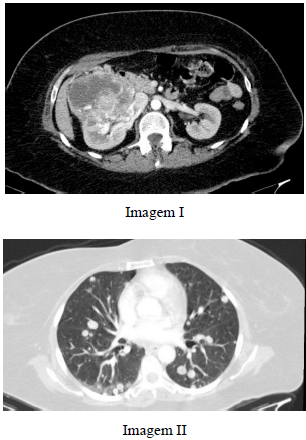

Paciente de 56 anos de idade com quadro de dor lombar e hematúria, sem febre ou alterações no leucograma, apresenta exames de tomografia computadorizada com as imagens I e II precedentes.

Considerando o provável diagnóstico de lesão renal para esse paciente, julgue o item seguinte.